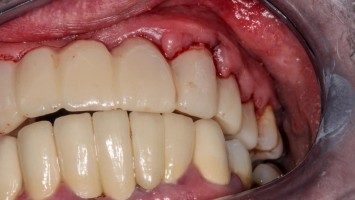

Bildnachweise